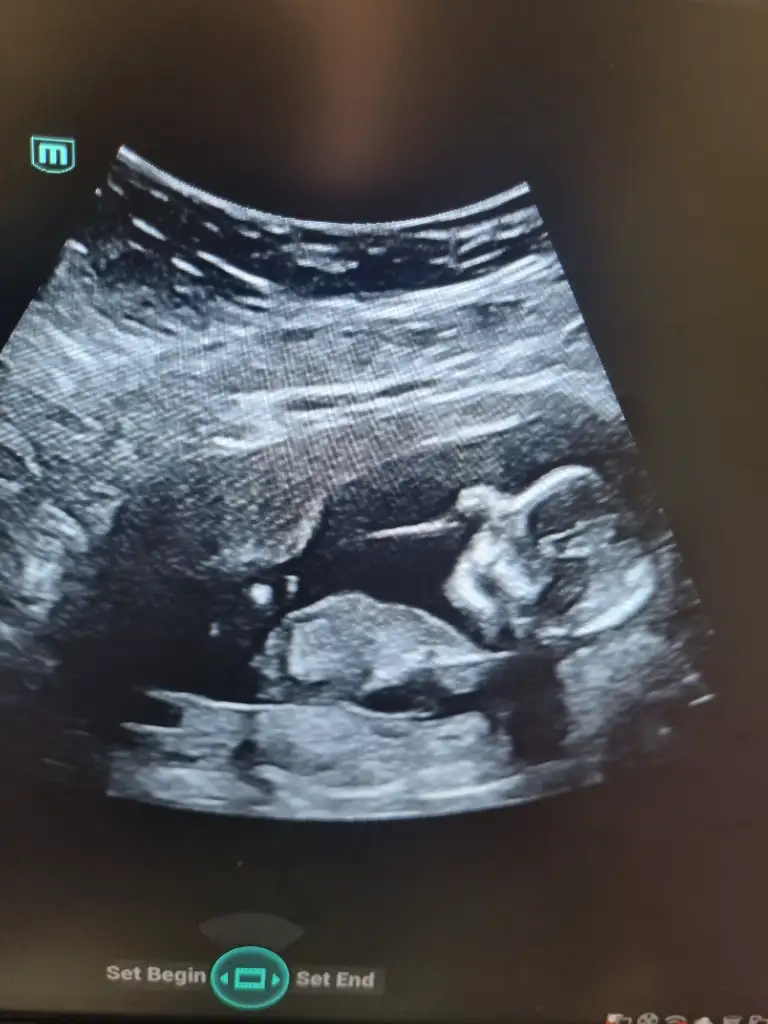

16 haftalık. Genital bölge fotoğrafı. yurtdışında olduğum için cinsiyeti de tam öğrenemedim. Anlarmısınız acaba?Bariz kız görüyorum, hayırlısıyla sağlıcakla gelsin inşallah![]()

Erkek olabilir16 haftalık. Genital bölge fotoğrafı. yurtdışında olduğum için cinsiyeti de tam öğrenemedim. Anlarmısınız acaba?

Neye göre acaba? Ben çok kararsız kaldım daErkek olabilir

Başka ultroson resmi varmıNeye göre acaba? Ben çok kararsız kaldım da

Yok. En son bir tek bu varBaşka ultroson resmi varmı

Sizinki de böylemi görünüyordu?Erkek olabilir

Benim erkek bebeğim olacak onda çıkıntı net gözüküyordu ama bunda bacak arası net görünmüyor bilemedim yani tahmin sadeceSizinki de böylemi görünüyordu?

Hem 3 çizgi hem Çıkıntı gibi bir şey gördü. O yüzden tam tahmin yapamadı. Bu haftada tam belli olmazmıydı. Erkek olsa görünmesi lazımdı ama bir az belleyelim dediBenim erkek bebeğim olacak onda çıkıntı net gözüküyordu ama bunda bacak arası net görünmüyor bilemedim yani tahmin sadece

Normalde belli olması lazımHem 3 çizgi hem Çıkıntı gibi bir şey gördü. O yüzden tam tahmin yapamadı. Bu haftada tam belli olmazmıydı. Erkek olsa görünmesi lazımdı ama bir az belleyelim dedi